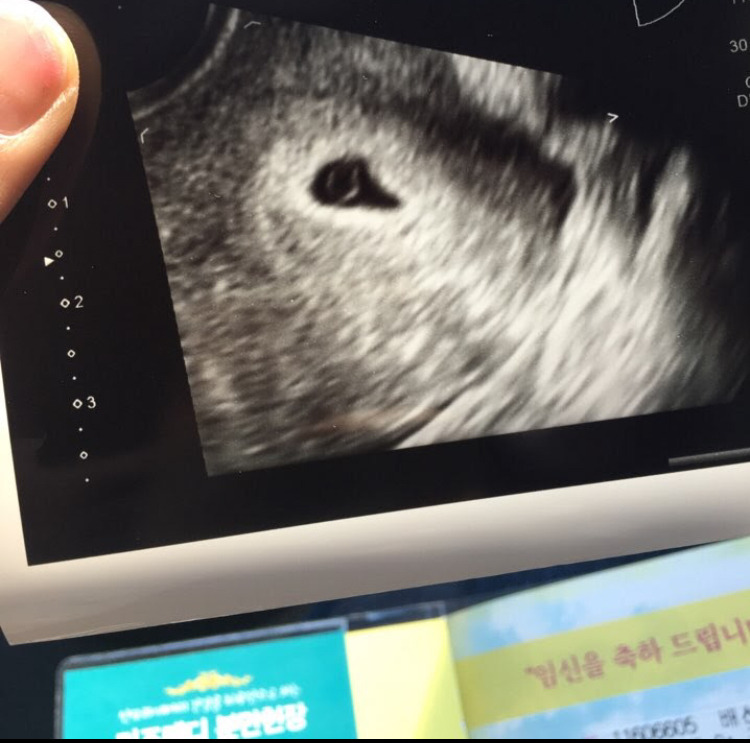

그리고 그 다음주인 5주차에 병원을 다시 찾아 첫 초음파를 보고 9주차에는 가슴 뭉클한 아이의 첫 움직임을 볼 수 있었다.